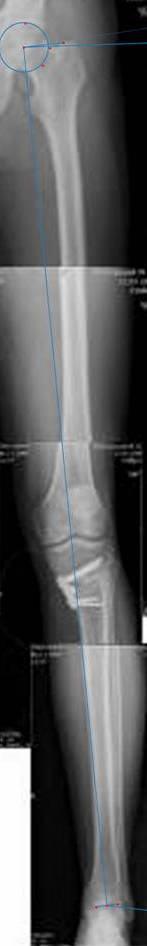

Я картинку собрал с некоторыми погрешностями, если провести отвес от центра вращения головки бедра до середины голени (на пациенте),то имеется небольшой вальгус (гиперкоррекция)конечно она (гиперкоррекция) не достигает 10 гр, но 5 гр она достигает.

К сожалению, не очень удачный пример. Если верить Р-граммам, имеет место быть дисплазия мыщелков бедренной кости с наклоном суставной линии. Это уже создает сложности получения хороших отдаленных результатов. Кроме того, по классике, необходима гиперкоррекция с созданием вальгуса 7-10 градусов для максимальной разгрузки медиального отдела КС. Если верить укладке, то линия сустава имеет четкий варусный наклон, поэтому результат операции м.б. кратковременным. В этих случаях показана двойная остеотомия бедра и тибии.

Если сделать правильно, то видно, что бедренная кость в порядке, а цель остеотомии (низкой, кстати), не достигнута вовсе.

Сохраняется варус. Для того, чтобы создать вальгусную гиперкоррекцию, не моделируя при этом откровенный Х голени, можно сделать медиализирующую остеотомию.

Ув.Александр.Как раз бедренная кость и не в порядке. Абсолютно прав проф.Р.М.Тихилов - "имеет место быть дисплазия мыщелков бедренной кости с наклоном суставной линии". Именно это определяет патомеханику процесса в суставе и пути её устранения. Тибиальная остеотомия - палеотив, ещё менее эффективна медиализация. Только двойная(или на двух уровнях) остеотомия исправит положение сустава и при данном (рентгенологическом) состоянии сустава, протез понадабиться глядишь лет через двадцать, а может вообще не понадобиться.